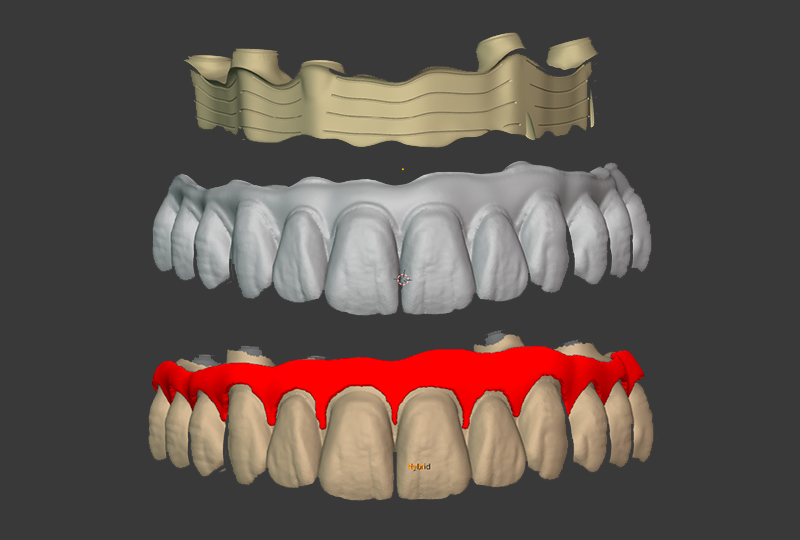

ODT Giovanni Rossi: Quando le scansioni arrivano al laboratorio, procediamo con due livelli di verifica: ripetiamo la scansione dell’arco per confrontare quelle del clinico con quelle del laboratorio e montiamo sull’arco di bloccaggio degli analoghi in gesso per creare una chiave di precisione (Figure 8, 9 e 10).

Accoppiamento "Only Top" delle librerie sulla scansione importata in cad

Fig. 8

Fig. 9

Concetto di De|Bug: utilizzando la ferula che incorpora gli ScanTransfer si costruisce una chiave in gesso con la posizione degli analoghi da laboratorio

Fig. 10

Le scansioni sono importate in Exocad per lo sviluppo del progetto protesico e per quello del modello stampato (Figure 11, 12). Il progetto protesico viene esportato da Exocad e importato in Blender per la riduzione della parte rosa e la separazione della barra primaria con il protocollo I-Bar (Figure 13, 14 e 15). Il modello viene stampato con la stampante Dental Makers LB4K 2.0 e resinaDental Makers Pro Model e Dental Makers Gum Mask. Gli analoghi a doppia vite garantiscono una posizione corretta. Effettuiamo comunque un check di verifica del modello con l’arco di bloccaggio creato da Diego (Figure 16, 17 e 18).

Passaggi in cad per la costruzione della iBar.

Fig. 11, 12